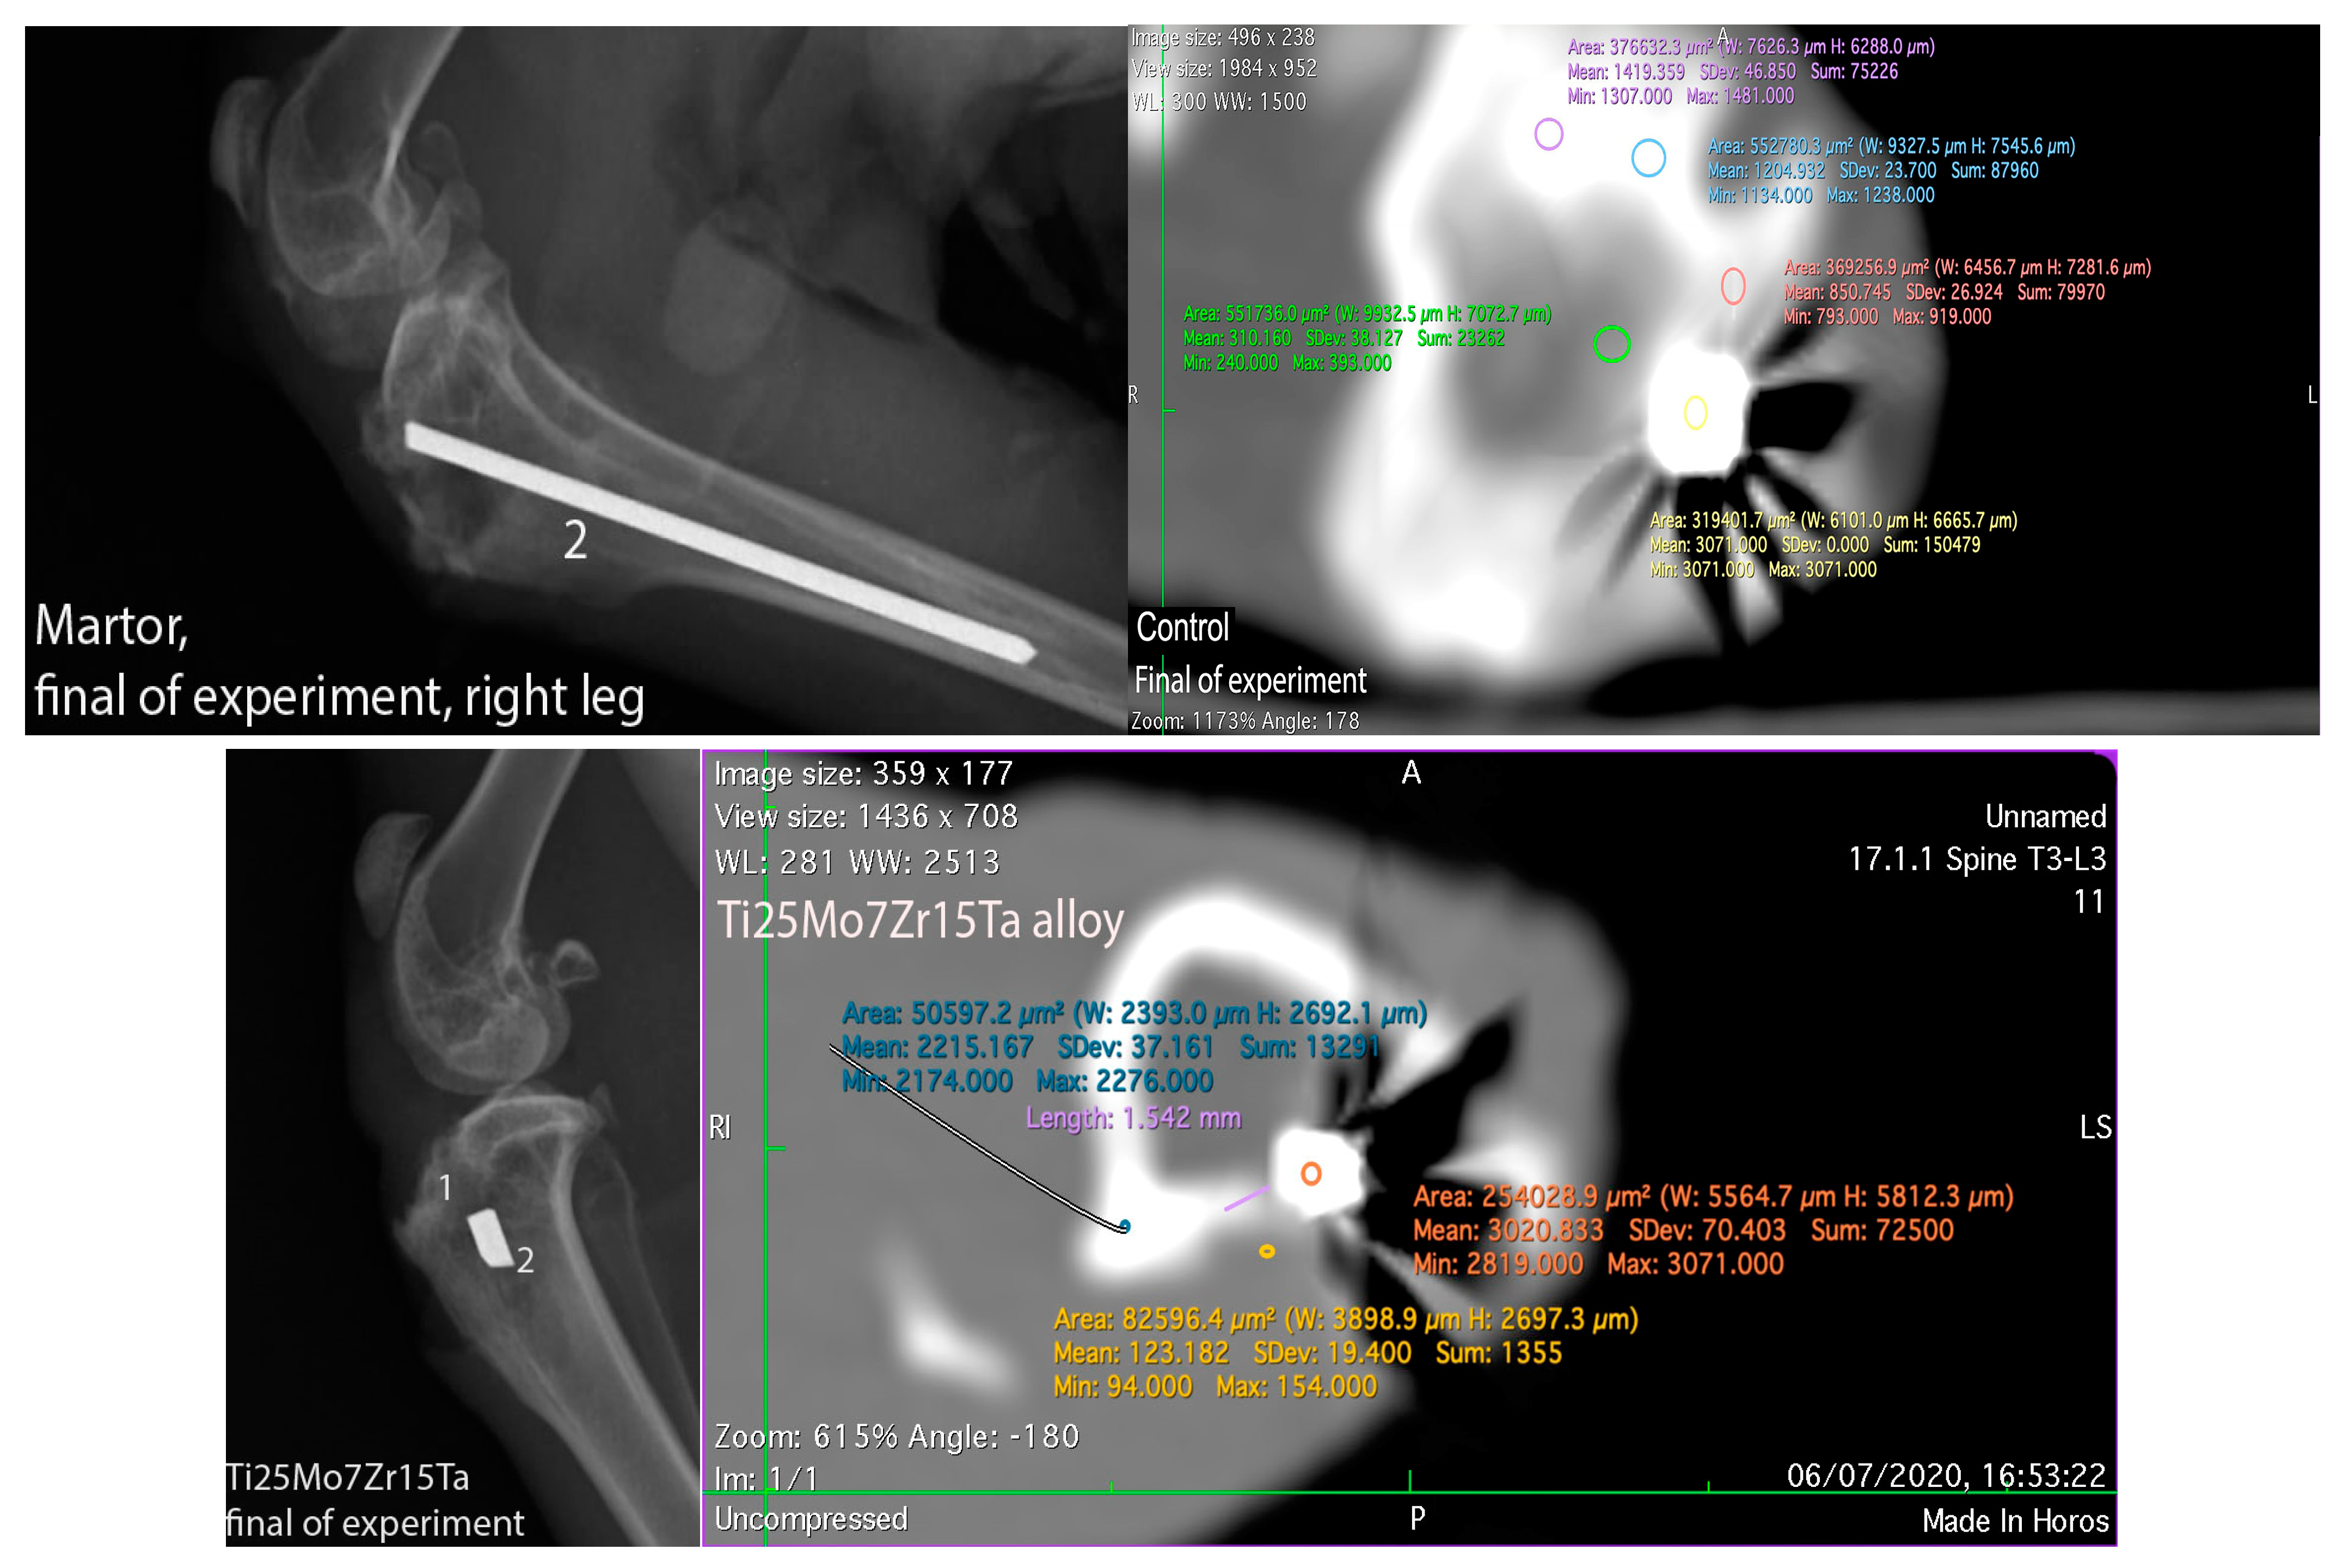

3.3. Interpretation of Results, Radiographs and Micrographs